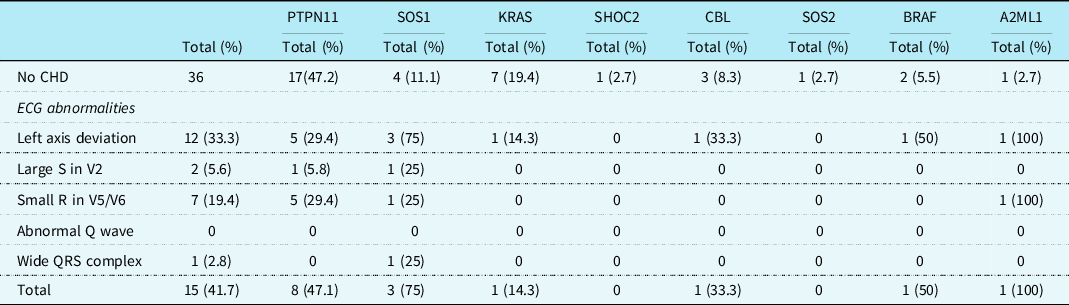

Table 1. Cardiac heart defects and ECG abnormalities in patients with Noonan syndrome

AI = aortic insufficiency; AS = aortic stenosis; ASD = atrial septal defect; AV = atrioventricular; AVSD = atrial ventricular septal defect; BAV = bicuspid aortic valve; CHD = congenital heart defect; CoA = coarctatio aortae; DCRV = double-chambered right ventricle; ECG = electrocardiogram; HCM = hypertrophic cardiomyopathy; MAPCA = major aortopulmonary collateral artery; MI = mitral insufficiency; PA = pulmonary artery; PS = pulmonary stenosis; TI = tricuspid insufficiency; VSD = ventricular septal defect.

In 60 patients (63.2%), one or more typical Noonan syndrome-related electrocardiographic features were seen. Most of the patients with CHD did show these typical Noonan syndrome-related electrocardiographic features (45/59, 76.3%). Also, in 15 of the 36 (41.7%) patients with a structurally normal heart on echocardiogram, typical Noonan syndrome electrocardiographic abnormalities were detected (Table 1). There was no significant difference in the incidence of the individual-specific Noonan syndrome-related electrocardiographic features between the group with CHD and the group without CHD, however, specific electrocardiographic features as a group occurred significantly more frequently in patients with CHD (p = 0.001).

There were 44 (46.3%) patients with left axis deviation, 29 (30.5%) patients with small R-waves in the left precordial leads, and 5 (5.3%) patients with large right precordial S-waves. An abnormal Q-wave was seen in 2 (2.1%) patients and a wide QRS complex also in 2 (2.1%) patients (Table 2). Typical Noonan syndrome-related electrographic features were not more often seen in patients with a mutation in the PTPN11 gene than in patients with other gene mutations. Patients with a mutation in the RAF1 gene had more frequently large S-waves in the right precordial leads (p = 0.002), and patients with SOS1 gene mutation had more frequent wide QRS complexes (p = 0.006).

Regarding the 36 patients without a CHD, 15 (41.7%) had specific Noonan syndrome-related electrocardiographic features. These electrocardiographic features were seen in patients with mutations in PTPN11, SOS1, KRAS, CBL, BRAF, and A2ML1 genes (Table 3). Left axis deviation was seen in 12 (33.3%) patients, small left precordial R-waves in 7 (19.4%) patients, large right precordial S-waves leads in 2 (5.6%) patients, and wide QRS complex in 1 (2.8%) patient (Table 3). One child with a SOS1 mutation without CHD had a complete left bundle branch block with left axis deviation with a septal flash on echocardiography (Fig 2a and b).

In this cohort, CHD was found in 62.1% and typical Noonan syndrome-related electrocardiographic features in 63.2% of Noonan syndrome patients. The typical Noonan syndrome-related electrocardiographic features were also present in 41.7% of patients without CHD. Left axis deviation was seen in 46.3% of patients, small left precordial R-waves in 30.5%, and large right precordial S-waves in 5.3% of the Noonan syndrome patients. There was no significant difference in the frequency of the individual- specific Noonan syndrome-related electrocardiographic features between the group with CHD and the group without CHD.